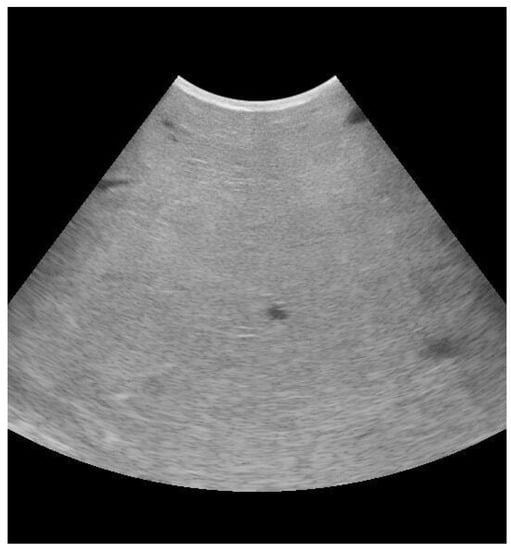

3.1. Mammary Ultrasound

- Fasulkov, I.R. Ultrasonography of the Mammary Gland in Ruminants: A Review. Bulg. J. Vet. Med. 2012, 15, 1–12. [Google Scholar]

- Suzuki, N.; Kurose, T.; Kaneko, S.; Haraguchi, A.; Isobe, N. Outcome Prediction from the First Examination in Clinical Mastitis Using Ultrasonography in Dairy Cows. Anim. Sci. J. 2020, 91, e13452. [Google Scholar] [CrossRef] [PubMed]

- Flöck, M.; Winter, P. Diagnostic Ultrasonography in Cattle with Diseases of the Mammary Gland. Vet. J. 2006, 171, 314–321. [Google Scholar] [CrossRef]

- Mourya, A.; Shukla, P.C.; Gupta, D.K.; Sharma, R.K.; Nayak, A.; Tiwari, A.; Singh, B.; Singh, A.P.; Sahi, A.; Jain, A. Ultrasonographic Alteration in Subclinical Mastitis in Cows. J. Entomol. Zool. Stud. 2020, 8, 2058–2063. [Google Scholar]